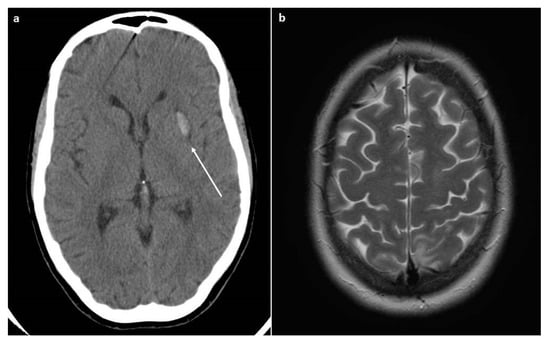

Soon after the CS, the patient underwent an eclamptic crisis (mean blood pressure value of 185/110 mmHg), and therapy with magnesium sulphate was started. She was admitted to the intensive care unit. A CT scan was performed due to the persistence of neurological symptoms (headache, scotomas, and confusion), and an intracerebral hemorrhage was detected, as seen in Figure 1.

Figure 1.

CT and MRI scans. (a) The CT scan revealed the presence of intracerebral hemorrhage (arrow). (b) The MRI scan (Axial T2-weighted image) revealed the presence of cerebral edema that is suggestive of PRES.

The day after, the patient referred to us a new onset of headache and visual disturbance; therefore, an MRI was performed, showing vasogenic cerebral edema, specifically in the axial T2-weighted images, suggestive of posterior reversible encephalopathy syndrome (PRES).